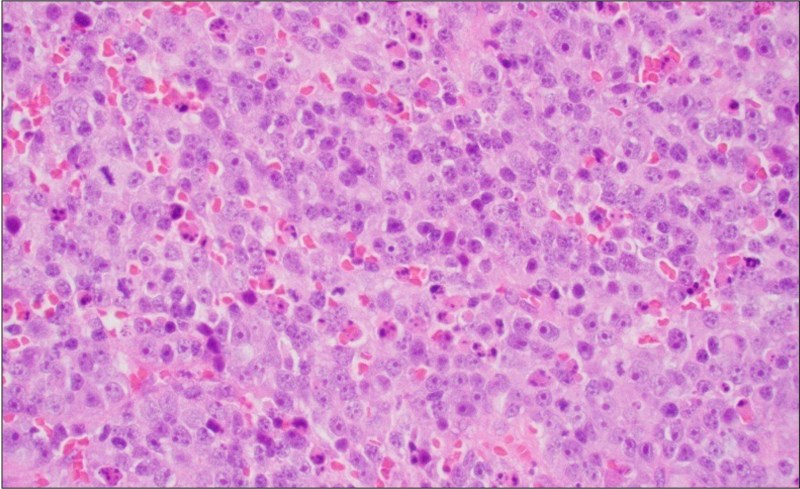

Light Microscopic Findings